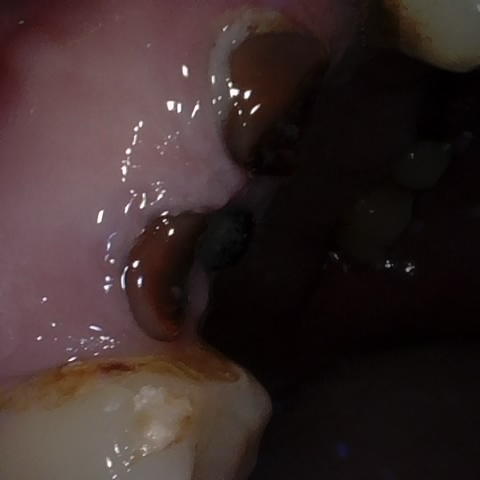

Annotated as "Good"